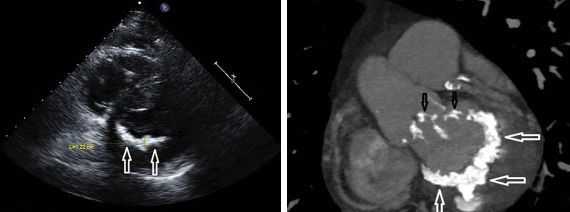

Другой важный инструментальный метод диагностики — эхокардиография (Эхо-КГ) . Эхо-КГ — это безболезненное ультразвуковое исследование, которое позволяет исследовать работу сердца в реальном времени. Эхокардиография покажет уменьшение эластичности клапана, его повреждение, размер отверстия митрального клапана и расстояние между его створками. Также при исследовании можно увидеть разрыв папиллярной мышцы и провисание клапанных створок в полость левого предсердия [4] [8] [9] .